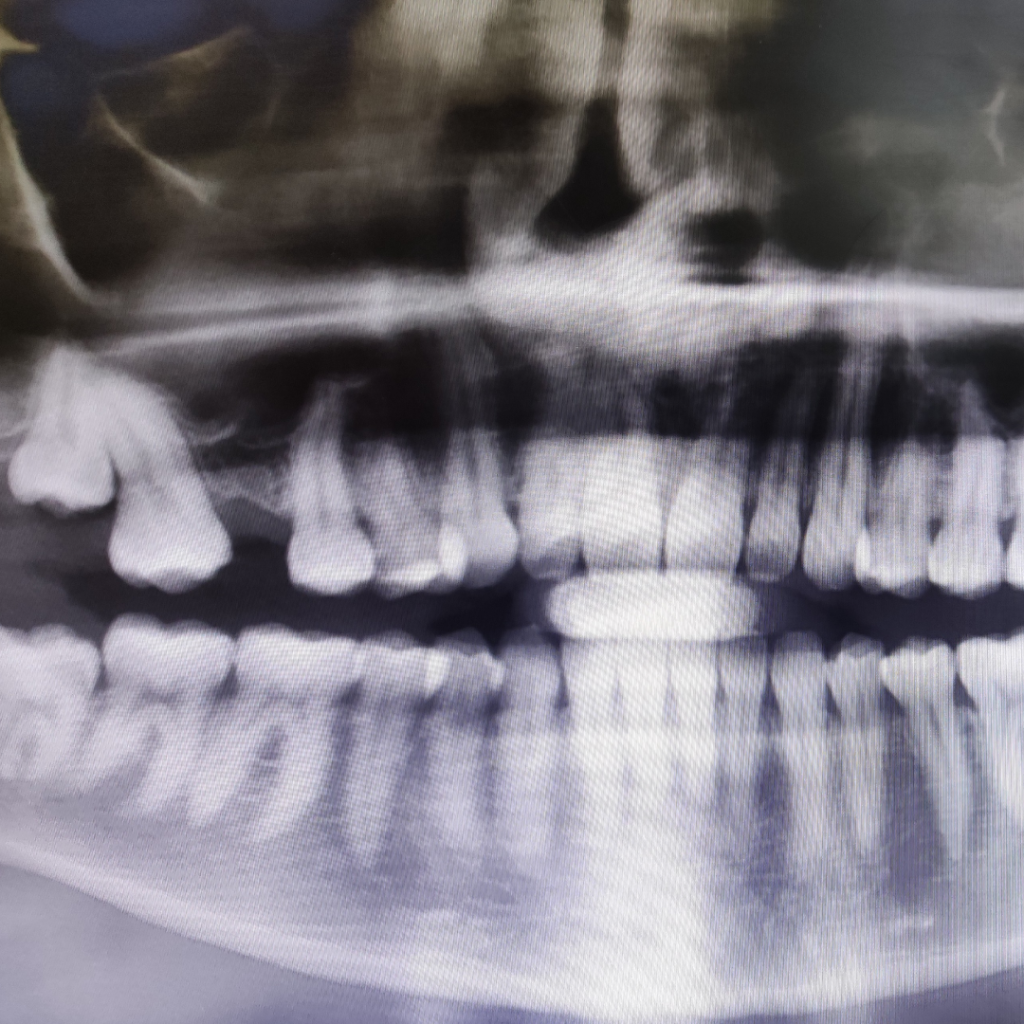

Из-за длительного отсутствия зуба у пациента сформировался дефицит костной ткани по высоте и произошло смещение 17 зуба в сторону отсутствующего.

Расстояние до верхнечелюстной пазухи составило менее 6 мм.